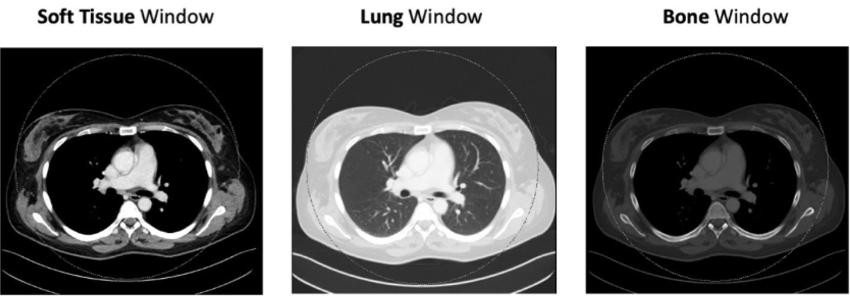

Skanningsvindue:

- De fleste CT-skanninger er i bløddelsvindue

• Bløddelsvindue: altid

• Lungevindue: ved thorax

• Knoglevindue: ved traume / mistanke om knoglepatologi